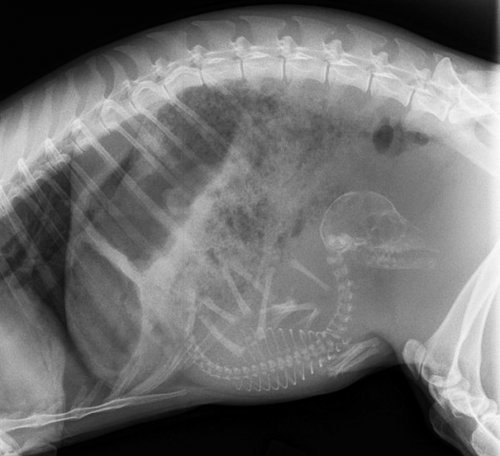

Итак, как выглядят рентгеновские снимки беременных животных:

морская свинка